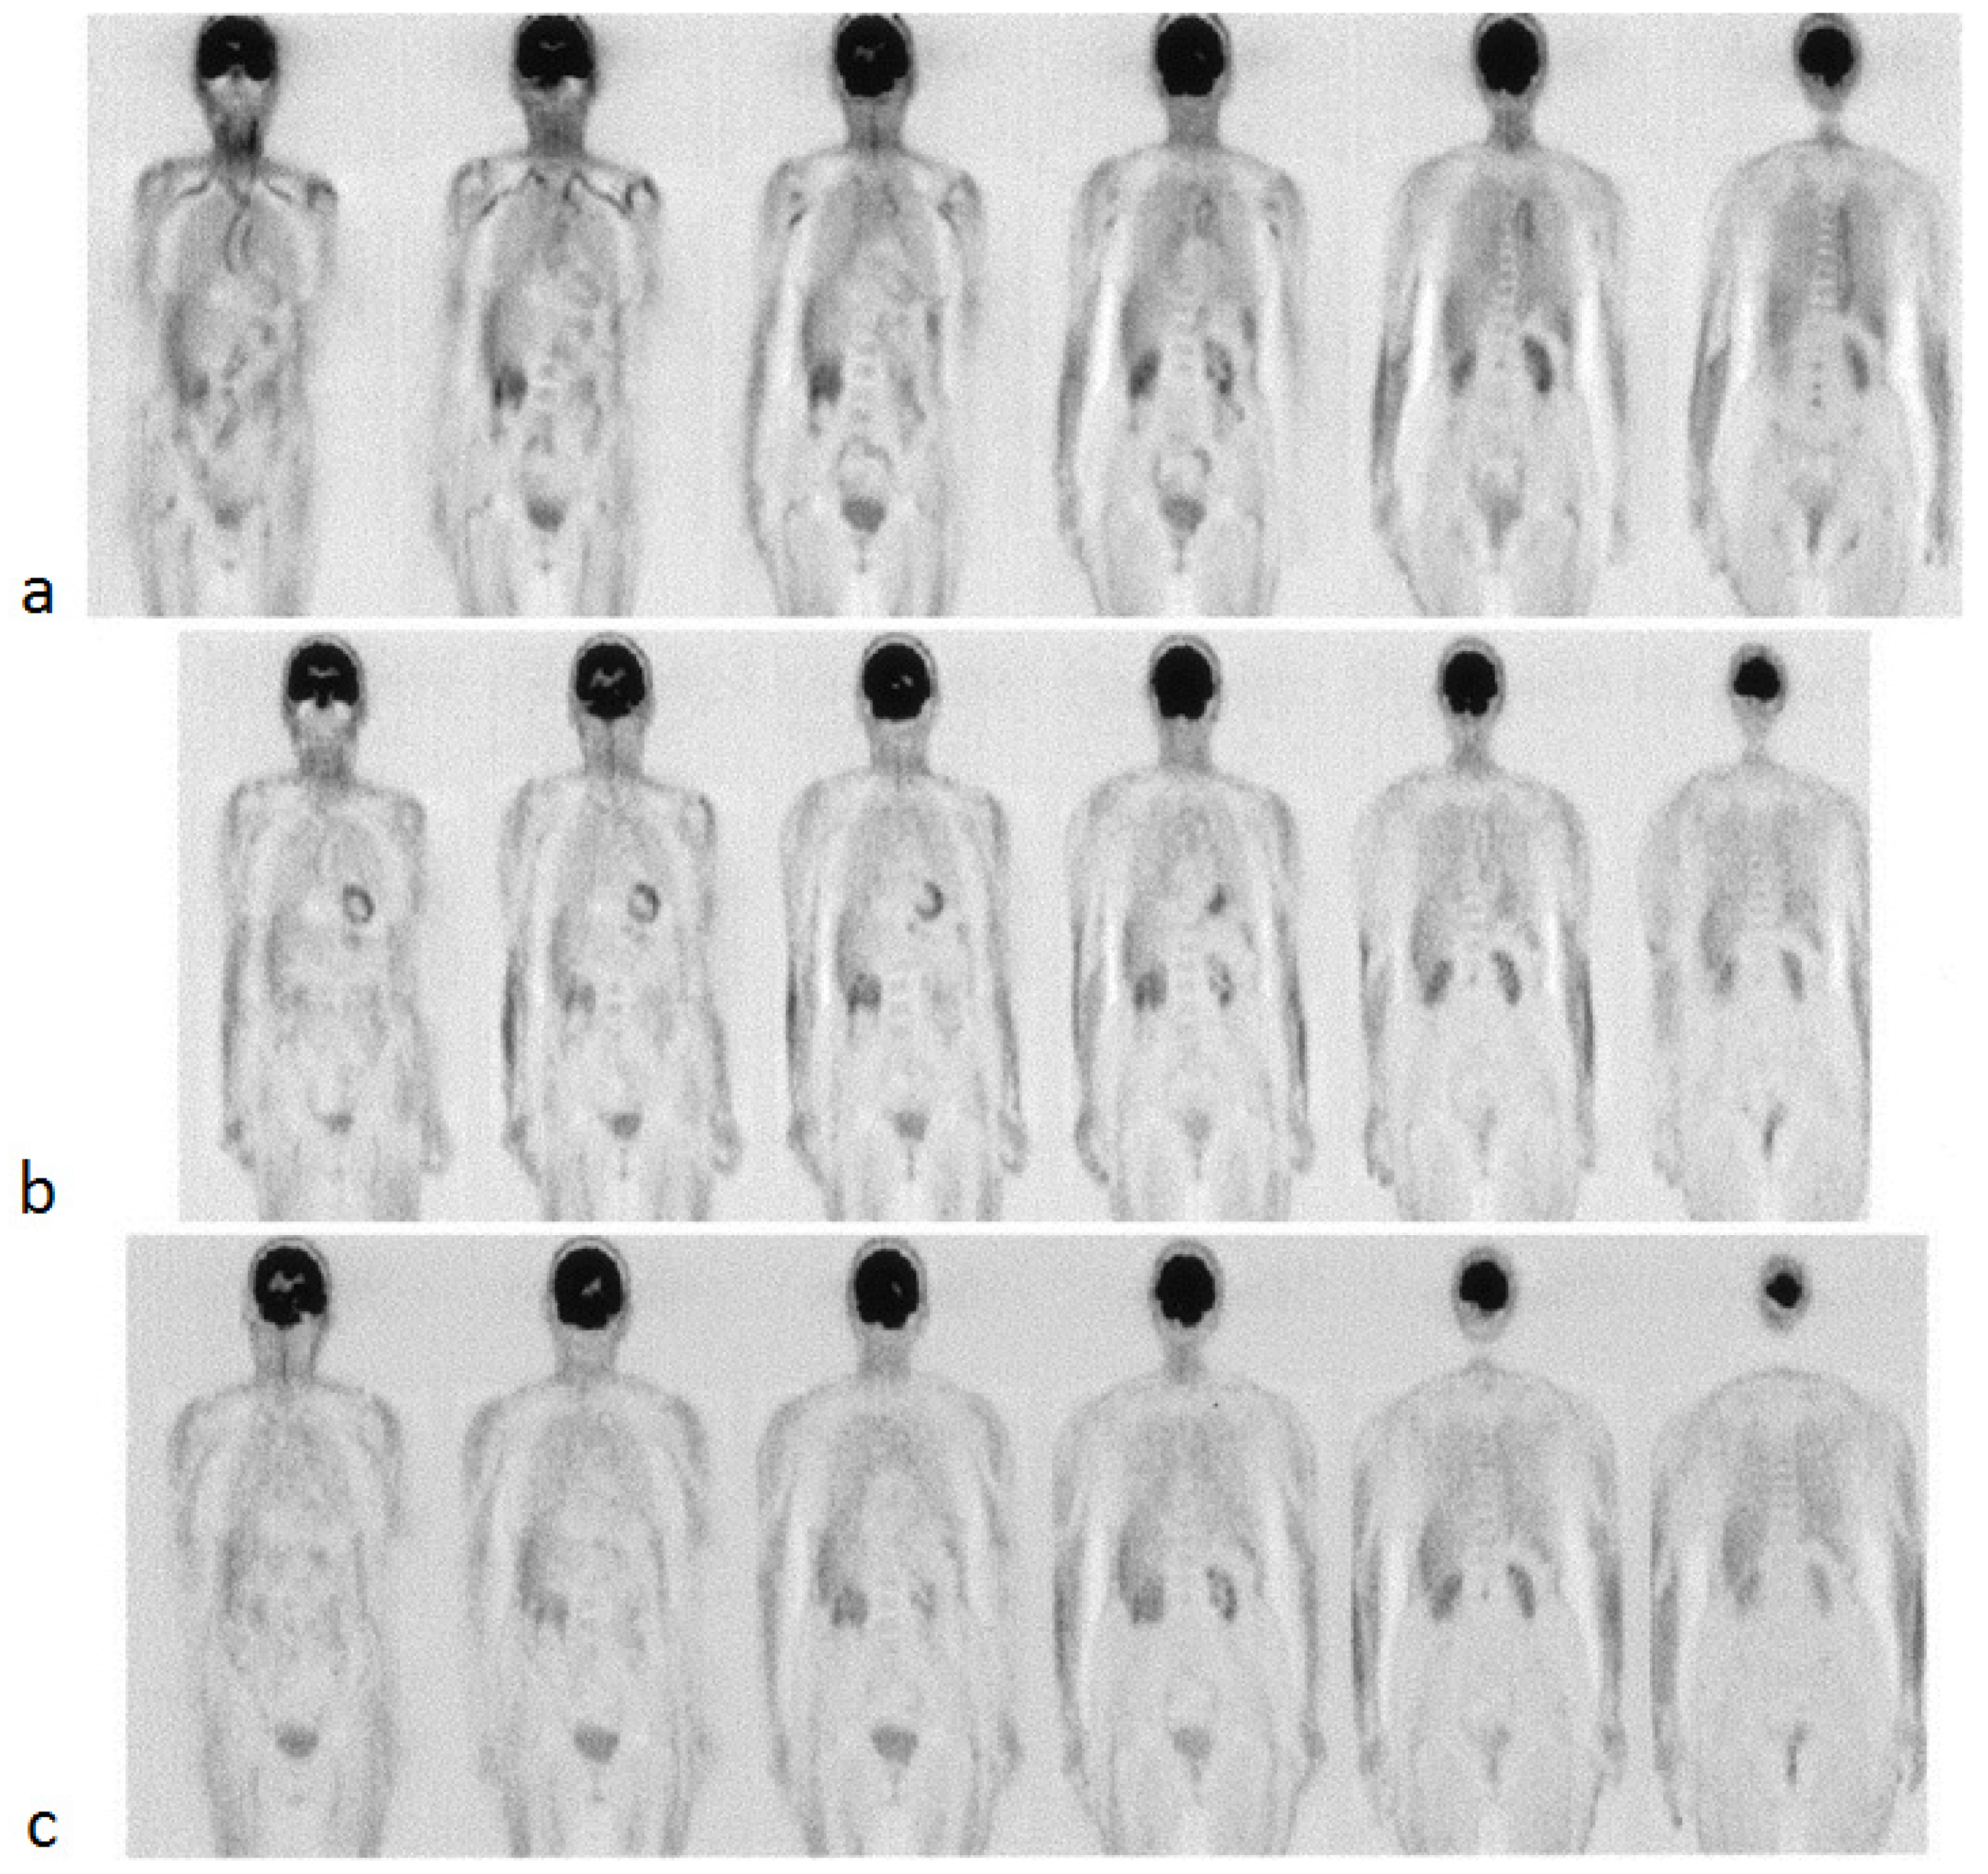

Several recent studies have proposed that FDG-PET/CT has a role in the diagnosis and monitoring of GCA [137,138,139,140,141]. In this disease, the symmetric involvement of the subclavian arteries and aorta often demonstrate increased FDG activity (Figure 5) [142]. A study by Sammel et al. considered 64 cases of suspected GCA and compared the imaging obtained within 72 h of starting glucocorticoids with the results of the temporal artery biopsy [139]. The sensitivity of FDG-PET/CT in the diagnosis of GCA was determined to be 92%, while the specificity was 85%. The importance of FDG-PET/CT in instances of suspected GCA with a negative temporal artery biopsy was evaluated in a study by Hay et al., who showed a large vessel uptake of FDG in 22 out of 63 such cases [140]. FDG-PET/CT has also been found to have a potential role in the diagnosis of TA, in which involvement of the left subclavian artery and bilateral carotid arteries is more common [135,143]. A prospective evaluation of 30 TA patients found that FDG could portray local inflammation and vascular remodeling [144]. A meta-analysis that included 191 TA patients across seven studies determined that FDG-PET had a pooled sensitivity of 87% and a pooled specificity of 73% [145].

Figure 5.

FDG-PET images of a 78-year-old woman with giant cell arteritis at the baseline (a), 3 months of therapy (b), and 6 months of therapy (c). High-tracer uptake is initially present and visible in the thoracic aorta and subclavian arteries, as evident in the first two images from the left (a), which progressively decreased after treatment with steroids (from Blockmans et al. [142] with permission).